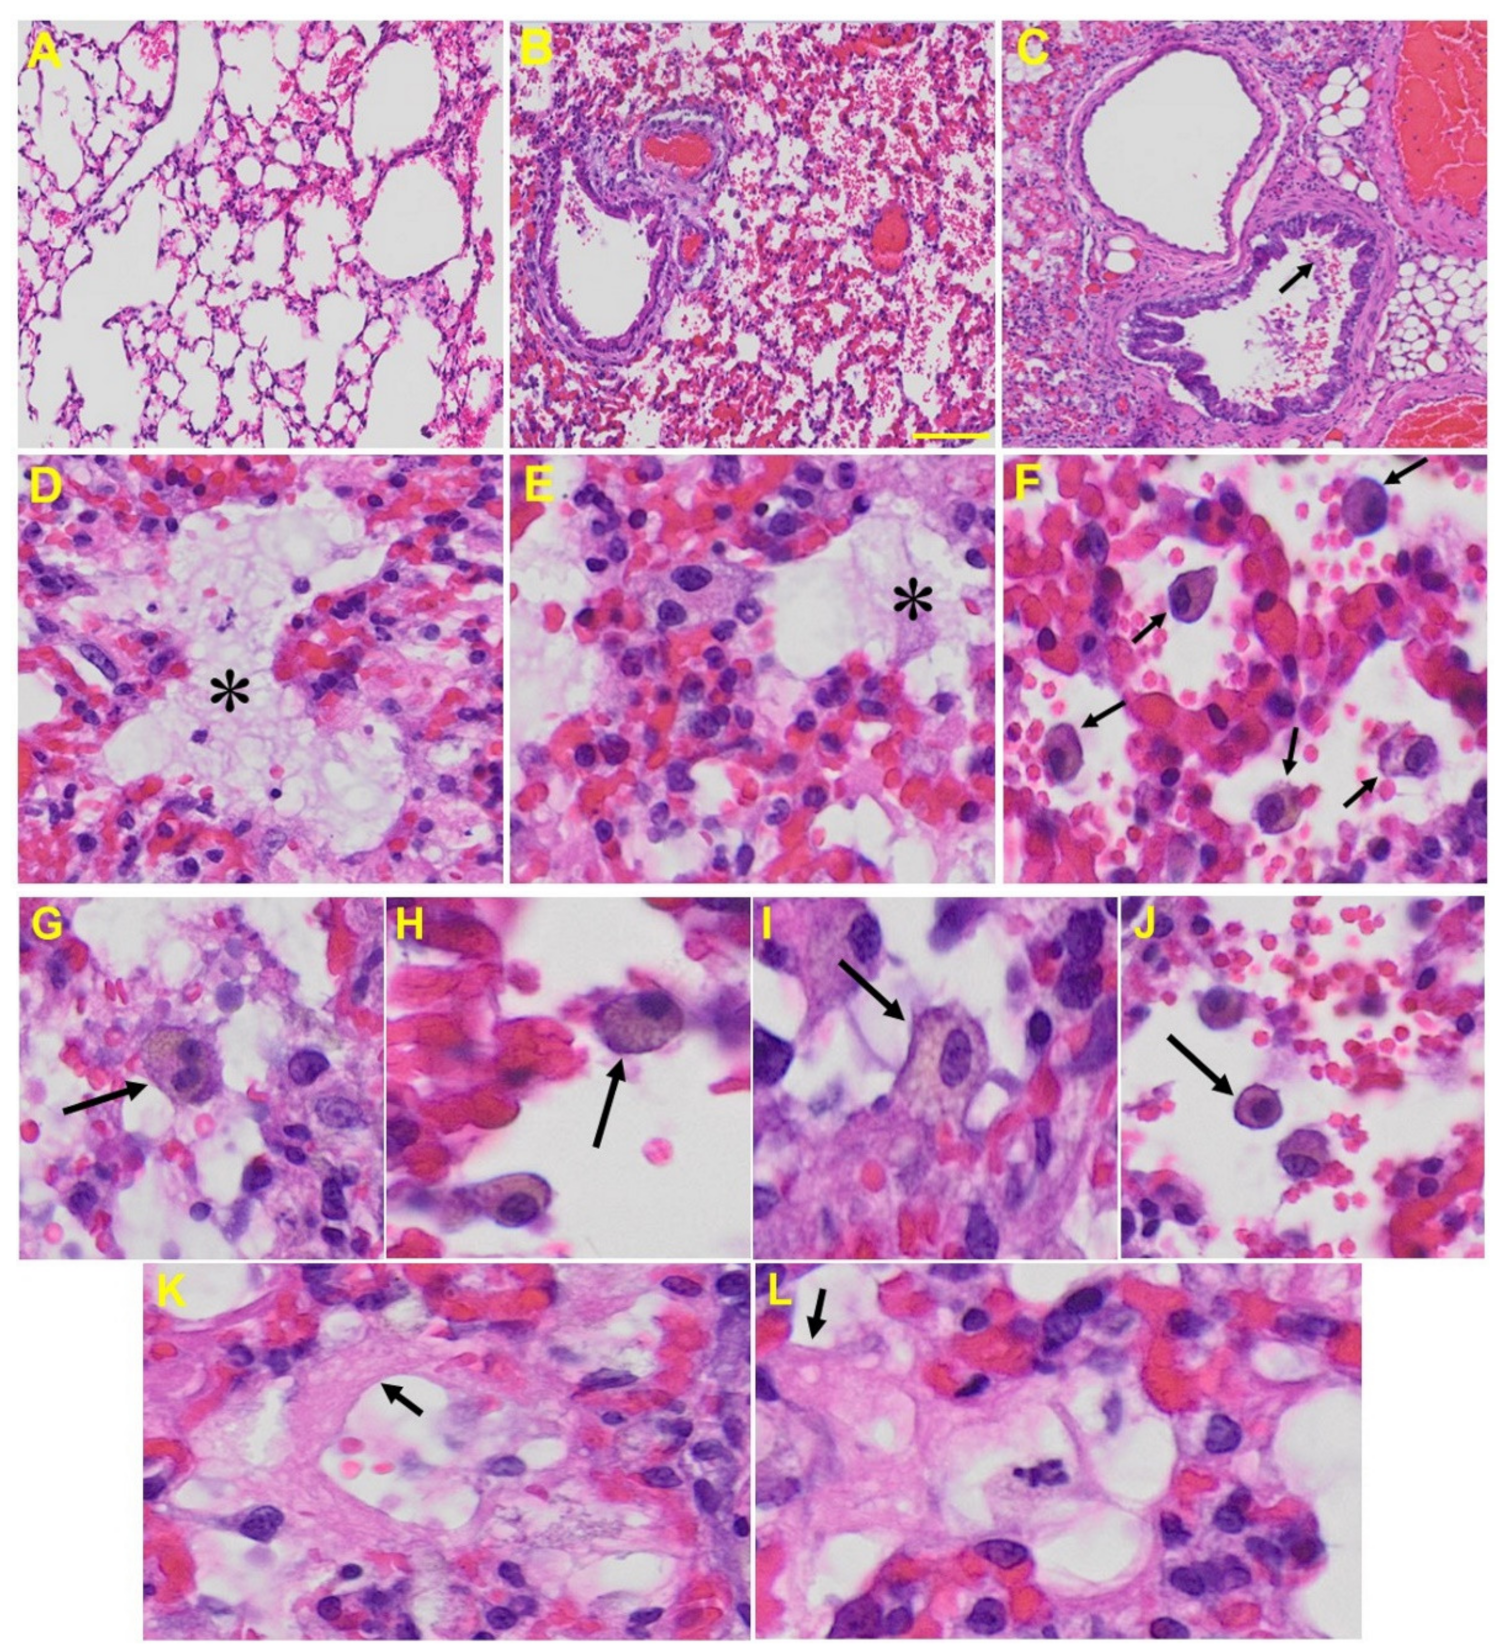

3.3. Histopathological Changes Post-MHV-1 Infection